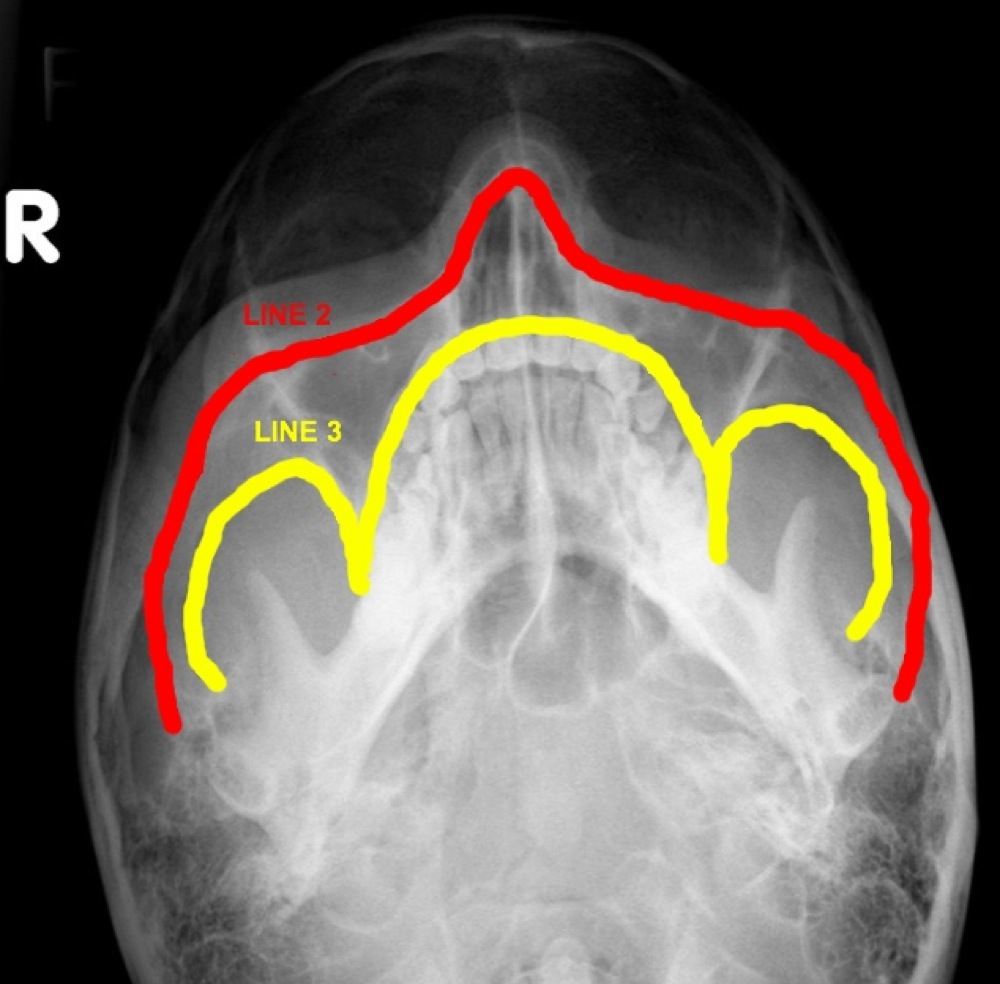

ON RADIOLOGY What are Occipitomental Views ? And lines for inspection. Facial Bones Om View Pa 30° (modified parietocanthial) occipito mental (om) (waters) occipito mental 30° (om30). This page contains radiographic anatomy of the adult facial bones. Familiarity with facial bone anatomy is required for accurate interpretation. The zygomatic arch looks like an elephants trunk on. Both the om and om 30 views will identify these fractures, along with the associated soft tissue swelling over. Facial Bones Om View.

ON RADIOLOGY What are Occipitomental Views ? And lines for inspection. Facial Bones Om View Familiarity with facial bone anatomy is required for accurate interpretation. Both the om and om 30 views will identify these fractures, along with the associated soft tissue swelling over the zygomatic eminence and. This page contains radiographic anatomy of the adult facial bones. • occipitomental (om) view at 0°: The zygomatic arch looks like an elephants trunk on. Pa 30°. Facial Bones Om View.

How To Read Facial Bone XRays By Peter Andre Soltau Jan2015 Facial Bones Om View Familiarity with facial bone anatomy is required for accurate interpretation. • occipitomental (om) view at 0°: Pa 30° (modified parietocanthial) occipito mental (om) (waters) occipito mental 30° (om30). The zygomatic arch looks like an elephants trunk on. This page contains radiographic anatomy of the adult facial bones. Both the om and om 30 views will identify these fractures, along with. Facial Bones Om View.

How To Read Facial Bone XRays By Peter Andre Soltau Jan2015 Facial Bones Om View Pa 30° (modified parietocanthial) occipito mental (om) (waters) occipito mental 30° (om30). The zygomatic arch looks like an elephants trunk on. Familiarity with facial bone anatomy is required for accurate interpretation. • occipitomental (om) view at 0°: Both the om and om 30 views will identify these fractures, along with the associated soft tissue swelling over the zygomatic eminence and.. Facial Bones Om View.